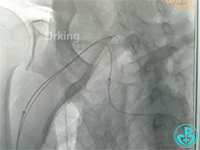

行冠脉造影,从肱动脉开始泥鳅导丝一直在影像中行进。造影结束,病人无不适主诉,返回病区前介入医生例行查看止血夹情况,无意中发现病人右侧颈部较左侧肿大,质软,无疼痛感,略觉胸闷感。立即行彩超检查显示颈部少量积液,右锁骨下动脉及头臂干未发现漏口。行胸部CT可见纵隔血肿,动脉CTA检查疑似头臂干分叉前有渗漏点。

行血管造影检查结果如下:

从影像上看似乎漏口在右锁骨下与右颈动脉分叉近端。